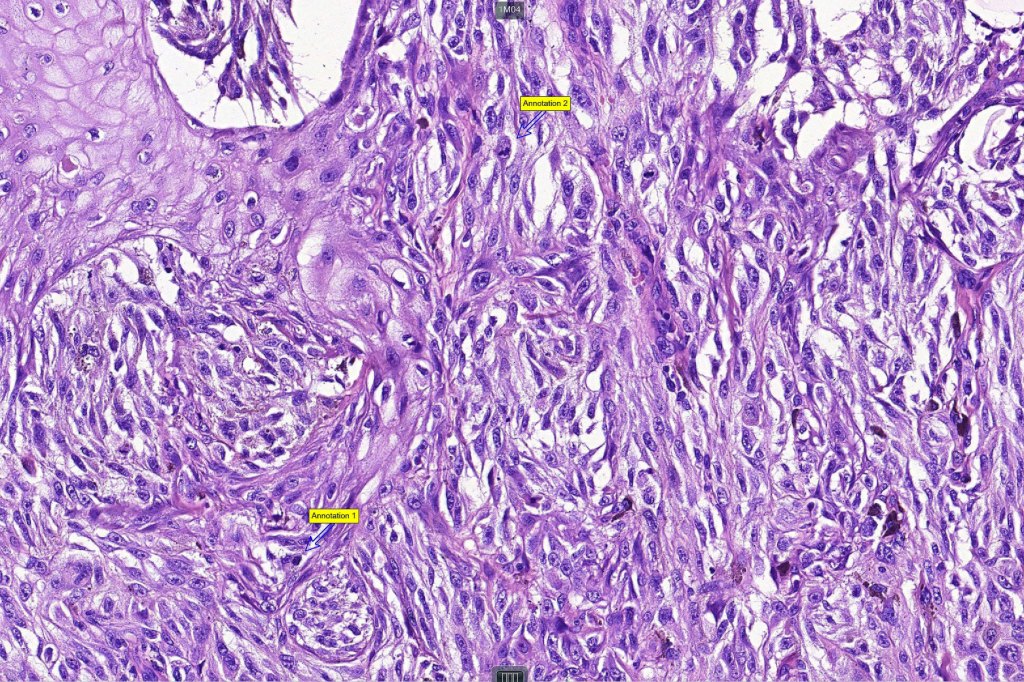

Histological features

•>5-10 mm

•Involve deep dermis or subcutis

•Asymmetrical, poorly circumscribed

•May show effacement/consumption of epidermis or ulceration

•Peripheral Pagetoid spread

•Large nodules which often show impaired maturation

•Loss of gradient with HMB45 and Ki67

•>20% Ki67 expression

•TERT promoter & PTEN mutations

•DNA copy-number variations